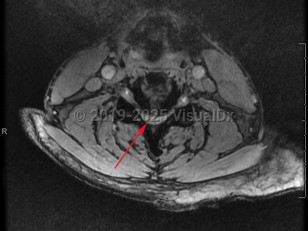

diflucortolone, 50-59 year old Female

231 Diagnoses match 0 of 1 findings